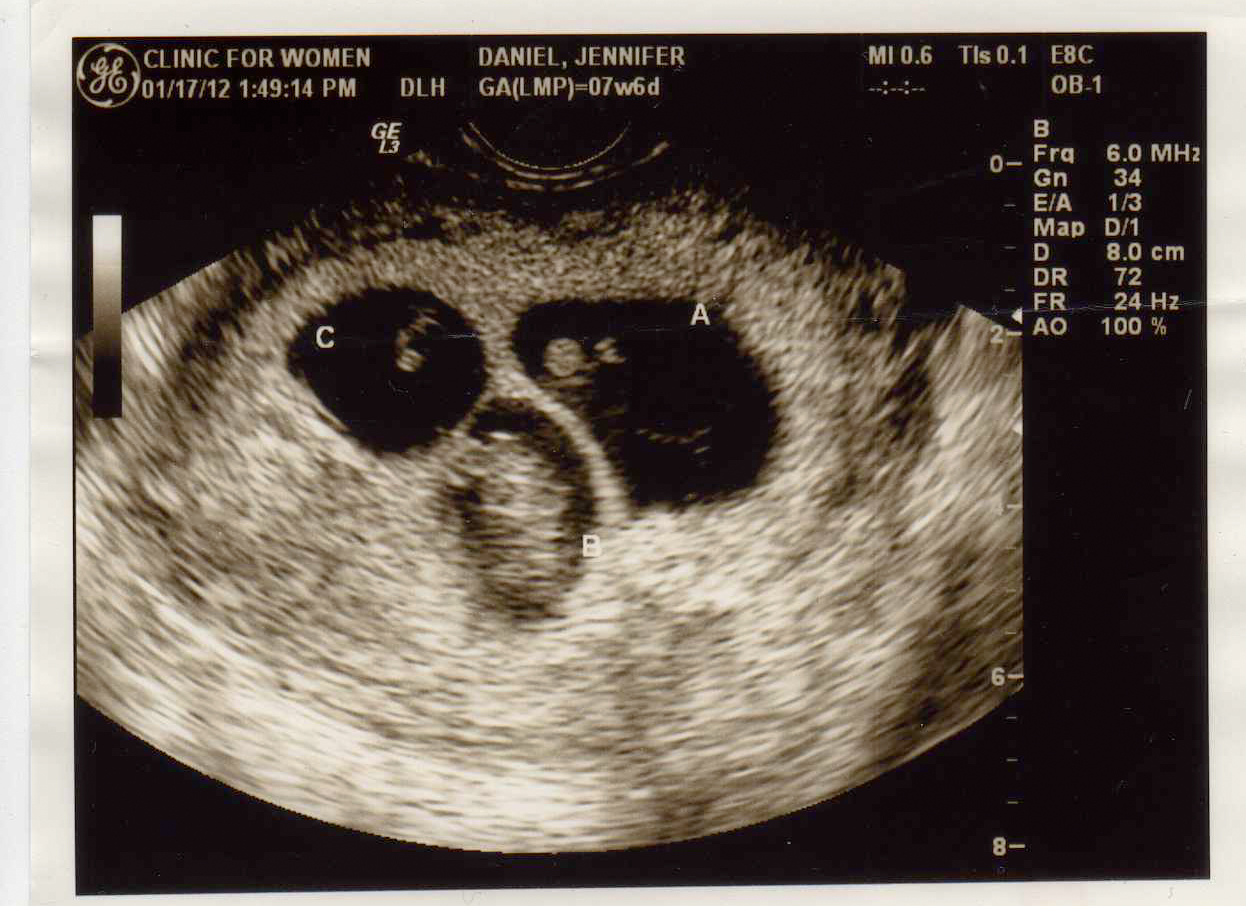

Best moment this week: Seeing our 3 active babies on the ultrasound.

Gender prediction: Girl, Girl, Boy (We hope!) or Boy, Boy, Boy!